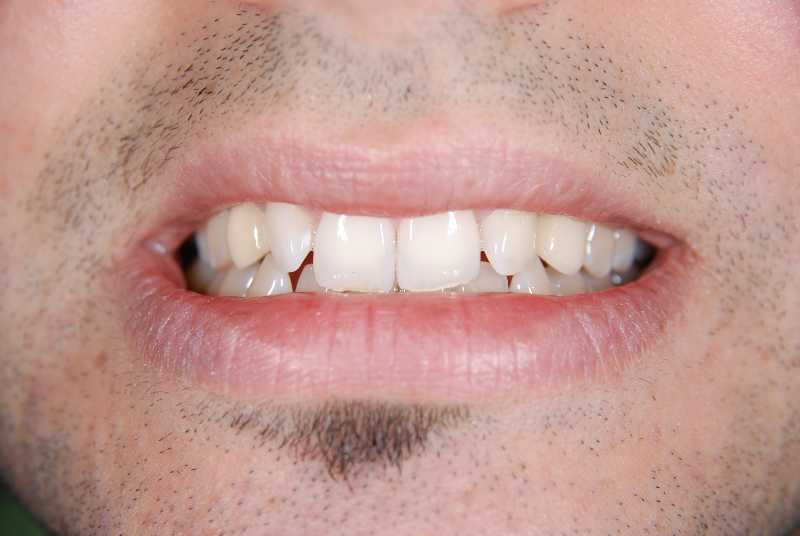

Intra oral view after placing the implants